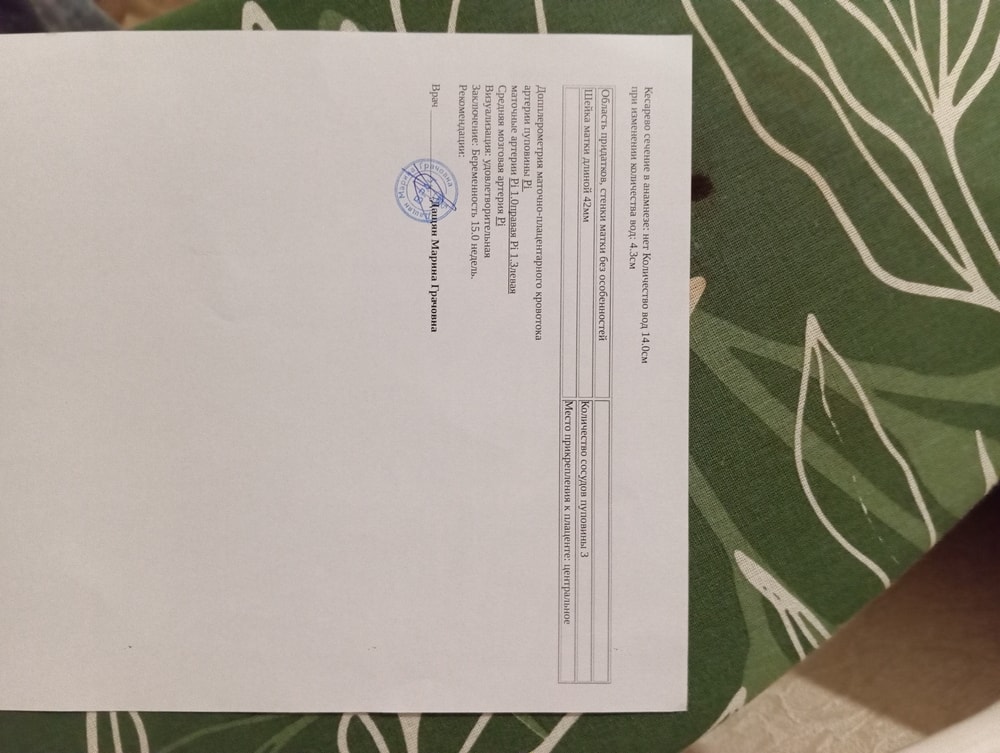

Как может быть 132 гр когда по всём таблицам 50-70 гр. Рост не указан. Сказали всё в норме, соответствует норме. Но мне не понятно.

Странное УЗИ, вес плода 15 нед и 0 дней